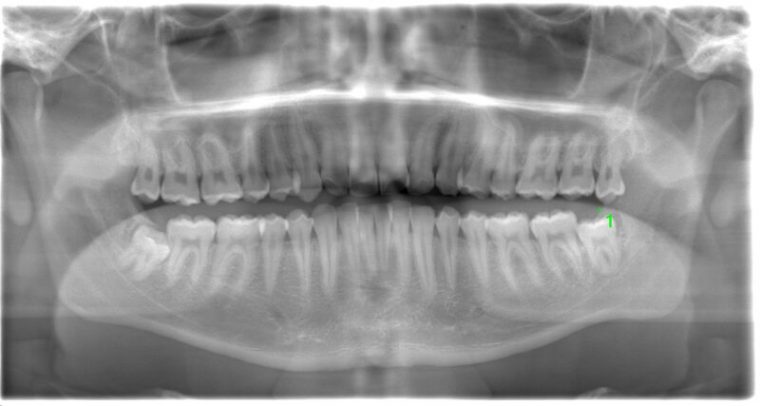

CASE 1

| 年齢・性別 | 30代・女性 |

|---|---|

| 主訴 | 左右に分けて親知らずを抜きたい、できれば痛くなく抜きたい |

| 親知らずのはえ方 | 完全に出ていてまっすぐはえている |

| 抜歯期間 | 15分 |

| 抜歯費用 | 約2,000円(保険内) |

| 抜歯内容 |

何度か虫歯になり痛みはないが早めに抜きたい。 完全に頭が出ているため歯ぐきを切ったり骨を削らずに抜歯しました。 根の形も単純なため抜歯自体は5分もかからず上下ともに終わりました。 術後痛みや腫れも出ていません。 抜歯後は感染をしやすいため必ず抗生物質を飲み切ってください。 |